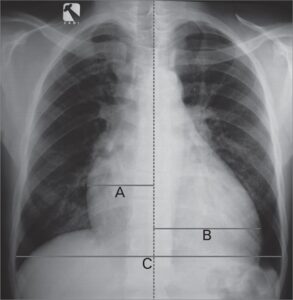

Hipofluxo pulmonar ûˋ a diminuiûÏûÈo do fluxo sanguûÙneo nas artûˋrias pulmonares, ou seja, menos sangue chega aos pulmûçes para ser oxigenado.

Na radiografia, os principais sinais sûÈo:

- ô Vasos centrais pouco calibrosos;

- ô Vasos perifûˋricos de calibre reduzido;

- ô CirculaûÏûÈo preferencial para a artûˋria pulmonar esquerda;

- ô Aumento localizado da artûˋria pulmonar;

- ô Sinais de aumento do VD;

- ô Hilo esquerdo mais proeminente que o direito;